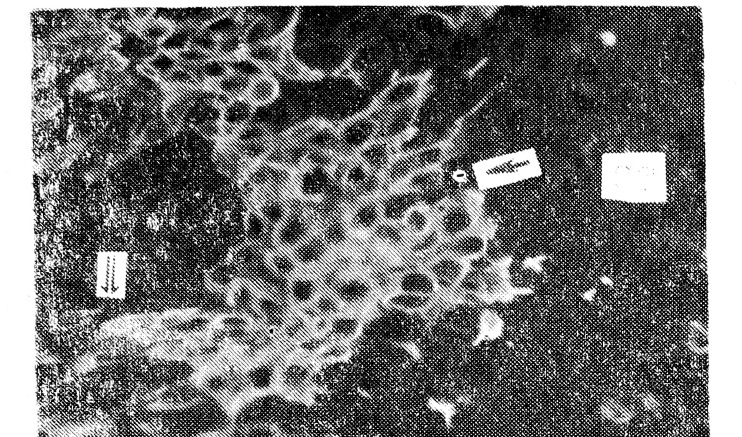

В нормальной слюнной железе миоэпителиальные клетки (МЭК) ацинусов и междольковых выводных протоков давали положительную реакцию с АТ к миозину, карбоангидразе III, кератину № 17. Железистые клетки ацинусов иммунореактивны только с АТ к кератину № 8, эпителий междольковых протоков — с АТ к кератину № 8 и ЭМА. В опухолевой ткани связывание указанных антител имеет отчетливую гистотопографию. Цилиндрический эпителий паренхимы аденолимфомы во всех случаях характеризуется положительной иммунореактивностью с АТ к кератину № 8 и ЭМА, причем эпителиальный мембранный антиген локализуется в апикальной части железистых клеток (рис. 1). Субэпителиальные клетки и очаги их пролиферации соответственно «подушкам Сандерсена» давали положительную реакцию с поликлональными антителами к миозину, карбоангидразе III (рис. 2) и МКАТ к кератину № 17. В лимфоидной строме опухоли выявлена отчетливая положительная реакция с МКАТ к Т- и В-лимфоцитам, при этом установлено, что В-лимфоциты располагаются в зоне реактивных центров, а Т-клетки — среди лимфоцитов, образующих мономорфную популяцию.

Рис. 1. Экспрессия ЭМА в акцикальной части цилиндрического эпителия железистого образования аденолимфомы (стрелка). ПАП методХ120.

Рис. 2. Положительная иммунореактивность с антителами к карбоангидразе III МЭК «подушек Сандерсена» (стрелка) и единичных клеток стенки кистозной полости (двойная стрелка). СТ — строма. Метод иммунофлюоресценцииХ220.